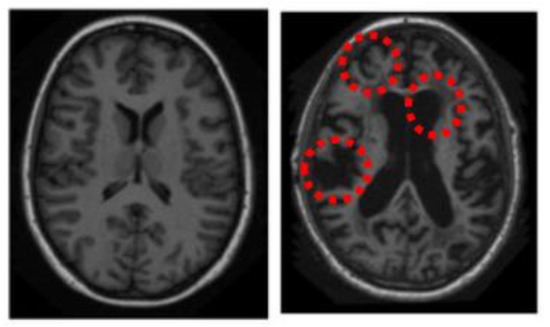

2.1. Pre-Processing

2.3. Generation of Saliency Maps

3. Results